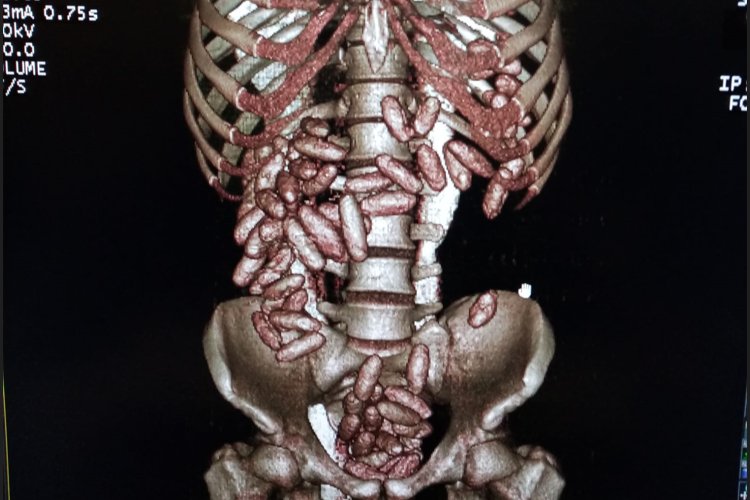

Gümrük Muhafaza ekiplerinin İstanbul Havalimanı’nda düzenlediği operasyonda uyuşturucu yutarak kuryelik yaptığı tespit edilen şahsın midesinde 820 gram kokain ele geçirildi.

Alınan bilgiye göre uçağın iniş yapmasının ardından muhafaza ekiplerince yolcuyu fiziki takibe başladı. Gümrük kontrol noktasında durdurulan şahsın beraberindeki valizi X-ray taramasından geçirildi ancak valizde herhangi bir suç unsuruna rastlanılmadı. Fakat ekiplerin üst araması yaptığı esnada şahsın telaşlandığı görüldü ve akabinde şahsın karın bölgesinde şişkinlik olduğu fark edildi. Bunun üzerine tomografi cihazına alınan şahsın çok sayıda kapsül yuttuğu tespit edildi.

Sağlık kuruluşunda yapılan muayene ortaya çıkarılan kapsüllerin içerisindeki maddenin kokain olduğu belirlenirken, kuryenin 820 gram kokain yuttuğu belirlendi.